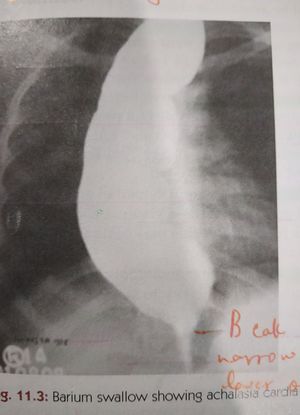

Achalasia cardia on #barium swallow